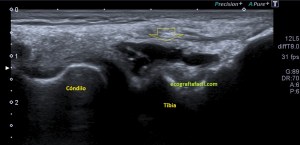

Lo primero de todo es saber cómo debemos ver un menisco en la ecografía, para ello debemos buscar la cara lateral, interna o externa que deseemos estudiar, con sonda lineal de alta frecuencia, corte longitudinal o eje largo respecto de la rodilla a estudio, es decir, como si hiciésemos un corte coronal de la misma.

Que debemos encontrar, bien, algo parecido a esto:

Esta es la normalidad, es una imagen preciosa cedida por Javier Álvarez @fisioequilibra, TSID, Fisioterapeuta, Profesor de la Universidad Francisco de Vitoria de Madrid, colaborador del Blog y amigo de los que se cuentan con los dedos de la mano…

Es lo primero que debes buscar, es lo más importante. En la imagen  1 puedes ver un menisco normal y sano, señalado por la flecha hueca amarilla. Semiológicamente es una estructura cónica hiperecogénica, homogénea en la cara externa de la rodilla entre la tibia y el cóndilo femoral, profundo al ligamento colateral, es la parte visible del menisco por ecografía y es tu objetivo en cada exploración de esta zona.

En el caso de hoy, el paciente presentaba una imagen de la zona descrita en la imagen 1 y que ves la imagen siguiente que difiere significativamente de la normalidad.

2

En esta imagen vemos la misma región que viste en la imagen 1, donde claramente ves alterada la semiología de la ecoarquitectura de menisco, heterogéneo, hundido, y en la superficie del mismo, imágenes hipecogénicas muy finas que pueden indicar afectación del mismo. Un poco más superficial e indicado con la flecha roja observas una estructura anecoica, correspondiente a líquido que luego verás en detalle en fotos posteriores.